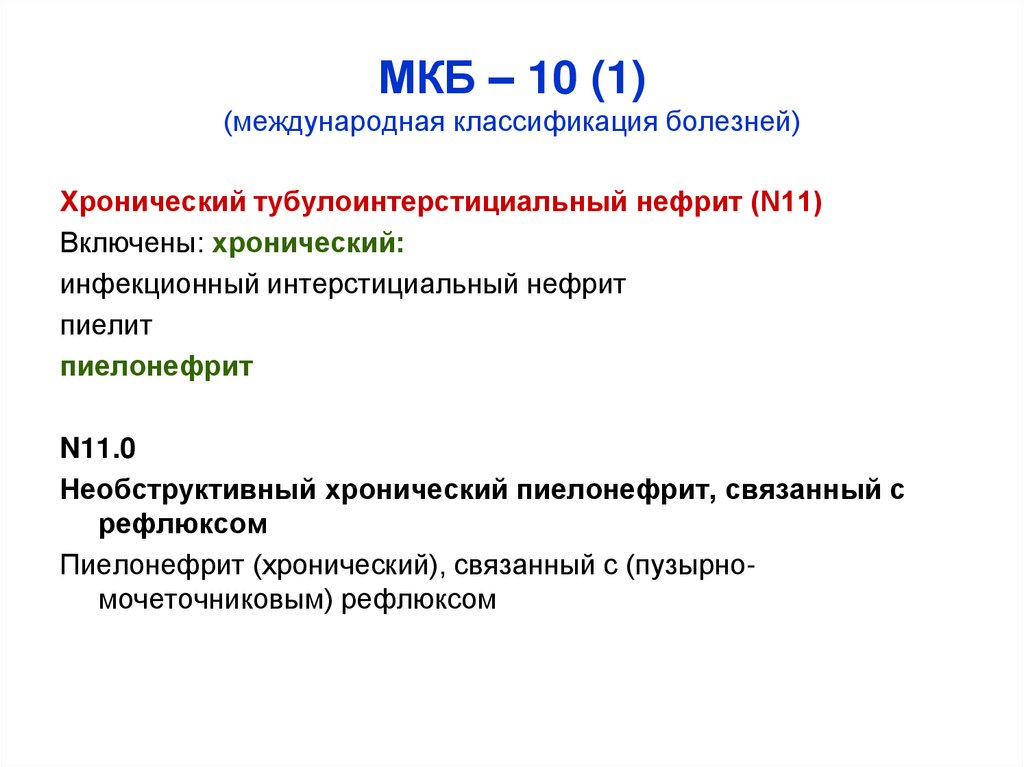

Код мкб 10 атерома головы

Код мкб 10 атерома головы 109 фото